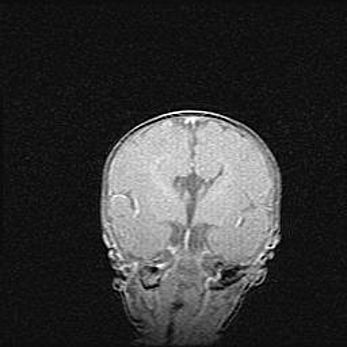

Неполная лизэнцефалия (пахигирия). Открытая гидроцефалия.

Возраст: 17 дней

Вес: 3110 г

Пол: мужской

Окружность головы: 33,5 см

Срок гестации: 35-36 недель

Лизэнцефалия—недоразвитие корковой пластинки и мозговых извилин в результате нарушения миграции нейронов коры. Поверхность мозговых полушарий гладкая. Микроскопически выявляется отсутствие нормальных слоев коры и скопление групп нейронов в подкорковом белом веществе.

Пахигирия—уменьшение числа вторичных извилин. В пораженном полушарии нервные клетки образуют толстый недифференцированный слой с неправильно расположенными нервными волокнами и группами гетеротопных клеток. Нервные клетки незрелые. Белое вещество истончено. При этом нередко аномально развит корково-спинномозговой путь.